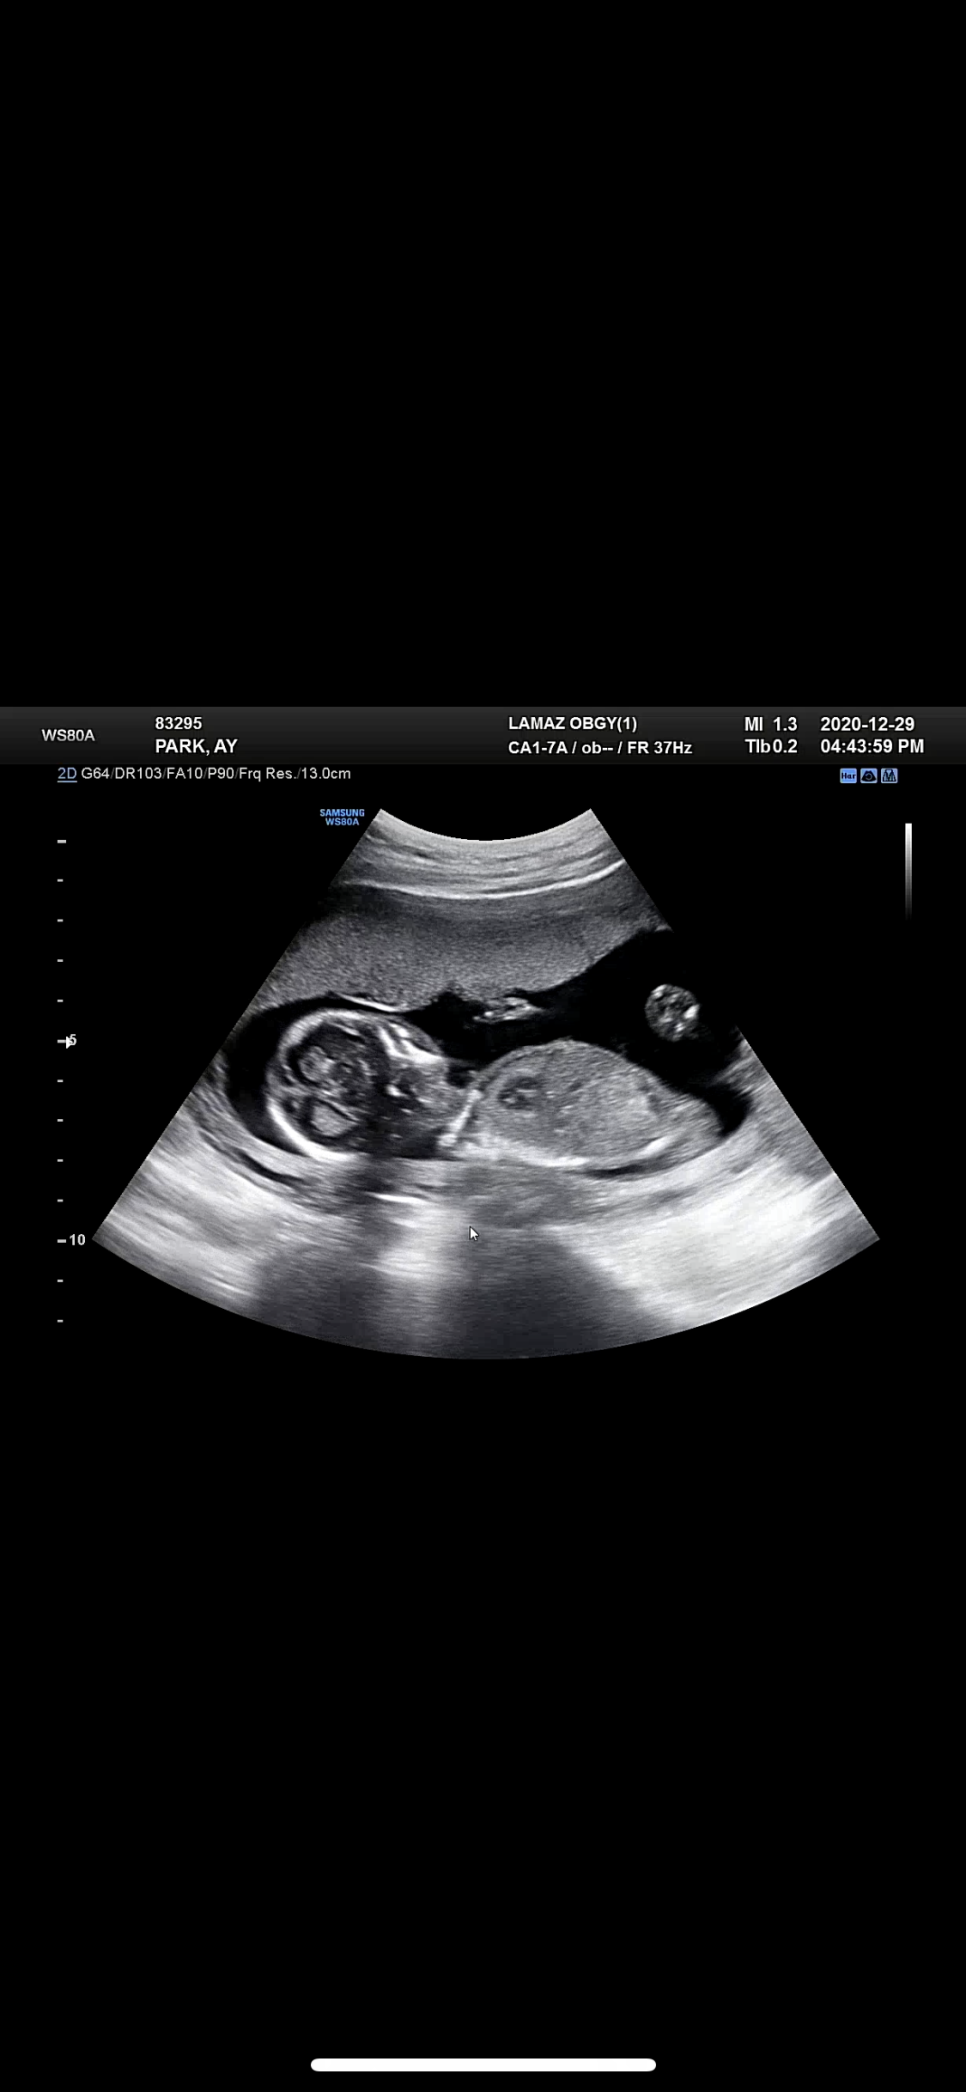

임신 16주 초음파

비비탄 콩알만 한 것이 손가락, 발가락이 자라고 세상에 척추까지 촘촘히 생긴 것을 보고 놀라고

임신 16주차, 배 크기가 왜 이렇게 큰지 알겠어요별똥별이 주수보다 크거든요 ^^…어쩐지 오빠 체격이 비슷한 것 같아요. wwwwwww

이 시기의 평균 아가 길이는 11-13cm / 60-120g

우리 별똥별은? 13.2cm / 126g

건강 그 자체입니다 ㅎㅎ